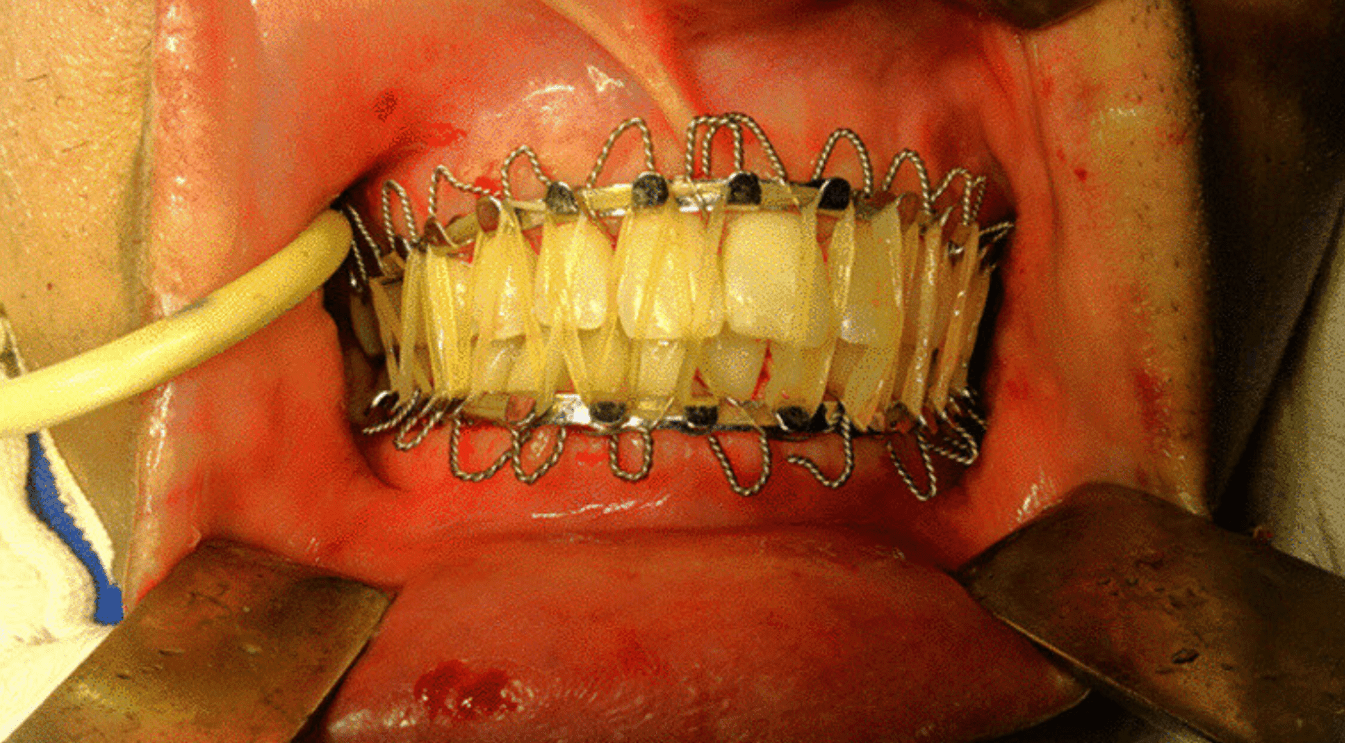

After his 2002 car accident, Kanye’s jaw was wired shut due to a comminuted mandibular fracture, a procedure known as intermaxillary fixation, which immobilizes the mandible by anchoring it to the maxilla so the bones can heal properly. If the fracture extended near the mental foramen and caused numbness of the lower lip and chin, the mental nerve was likely affected. Before giving rise to this nerve, the parent branch enters the mandible through a foramen located on which part of the bone?

Answer: Ramus of the mandible